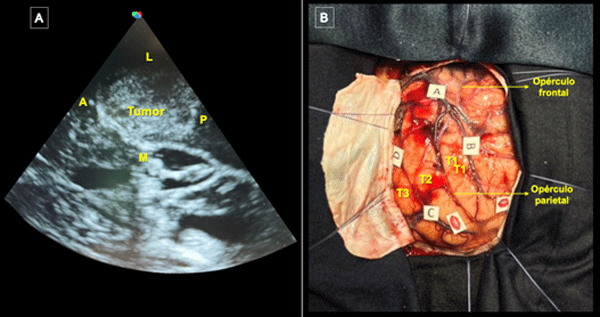

La incisión se centró en el punto temporal posterior (Figura 3), realizándose una herradura frontotemporooccipital izquierda y una cuidadosa hemostasia del colgajo. Craneotomía frontotemporal izquierda. La duramadre fue infiltrada con lidocaína al 1%. Posterior a ello se efectuó una durotomía arciforme con pedículo hacia basal exponiendo el giro temporal superior y medio. Con la paciente despierta se hizo ecografía intraoperatoria para delimitación de los márgenes tumorales, los cuales se identificaron con “tags” (Figura 4).

Figura 4. Ecografía intraoperatoria y mapeo cortical. A) Utilización de guía ecográfica intraoperatoria para identificar tumor y delimitar sus márgenes (A: Anterior; L: Lateral; M: Medial, P: Posterior). B) Marcación de los límites del tumor con tags de letras (A: Anterior; B: Medial; C: Posterior; D: Inferior) y de las áreas de mapeo positivo con presentación de anomia con dos tags de boca en región posterior de T2. Se expusieron también los giros temporales superior (T1), medio (T2) e inferior (T3) y se optó por corticotomía trans-T2.

Con la paciente despierta, se realizó estimulación cortical utilizando multitarea con flexión y extensión de miembro superior derecho combinando prueba de secuencias automáticas, test de nominación (Boston) y asociación semántica (PPTT). Para ello, se utilizó estimulación bipolar con pulso de onda cuadrada bifásica, de 1 ms de duración y frecuencia de 60 Hz. Se identificó el umbral de estimulación en 3.0 mA tras inducirse anomia en la región posterior de la circunvolución temporal media (T2).(13) Se identificaron áreas de mapeo positivo con los respectivos tags, delimitándose el acceso seguro a través de la porción media del giro temporal medio (ver Figura 4 B).